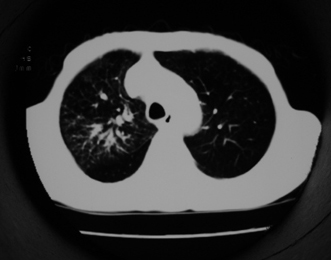

以下是引用同在2007-1-27 14:13:00的发言:[br]支持右侧中央型肺癌伴阻塞性病变.

以下是引用zjzjr在2007-1-27 16:56:00的发言:[br]支持右肺中心型肺癌伴阻塞性肺炎.